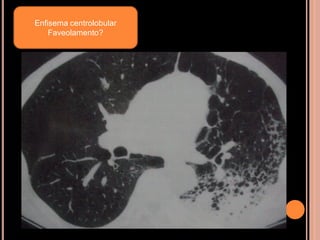

Enfisema centrolobular

Faveolamento?